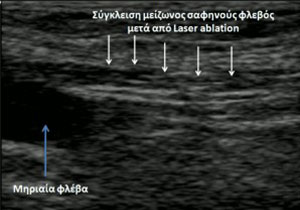

Η θεραπεία των κιρσών με ενδοφλέβιο Laser* είναι μία σχεδόν αναίμακτη επέμβαση που πραγματοποιείται με τοπική αναισθησία, υπό υπερηχογραφική καθοδήγηση, με ασφάλεια και ακρίβεια. Από την περιοχή της κνήμης εισάγεται διαδερμικά στη σαφηνή φλέβα η οπτική ίνα του Laser, η οποία προωθείται κεντρικά ως το ύψος της σαφηνομηριαίας συμβολής. Καθώς η οπτική ίνα αποσύρεται προοδευτικά, διαχέει ακτινικά ενέργεια, η οποία συρικνώνει ομοιογενώς τα φλεβικά τοιχώματα και σφραγίζει πλήρως τη φλέβα. Μετά το κλείσιμο της πάσχουσας φλέβας η κυκλοφορία αποκαθίσταται μέσα από τις υγιείς φλέβες του δικτύου.